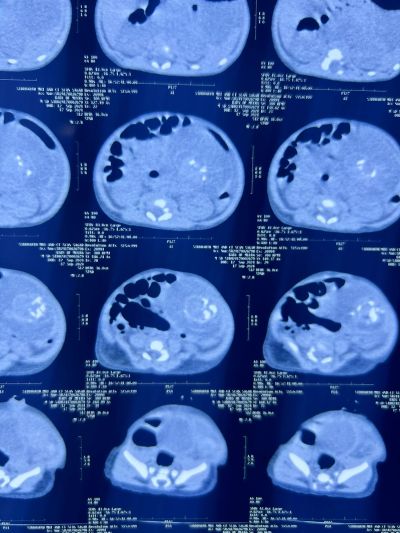

सागर. सागर के जिला अस्पताल में अचंभित करने वाला मामला सामने आया है। जहां नवजात के पेट में भ्रूण जैसी आकृति दिखने से डॉक्टर्स हैरान हैं। यह भ्रूण है या टेराटोमा ट्यूमर इसकी जांच विशेषज्ञ डॉक्टर्स कर रहे हैं। बच्चे के पेट में बच्चा होने की स्थिति बेहद रेयर होती है जिसे मेडिकल भाषा में फीट्स इन फीटू कहा जाता है। हालांकि स्वास्थ्य विभाग जांच के बाद ही स्थिति स्पष्ट करने की बात कह रहा है। स्वास्थ्य विभाग की क्षेत्रीय संचालक डॉक्टर ज्योति चौहान ने बताया कि केसली की महिला बीते दिनों जब सीटी स्कैन व सोनोग्राफी कराने सागर आई थी तो उसके पेट में पल रहे बच्चे के पेट में भी कुछ ट्यूमर या अविकसित भ्रूण जैसी आकृति दिखी थी। उसे जिला अस्पताल में ही प्रसव कराने की सलाह दी थी, लेकिन दो दिन पहले महिला का प्रसव केसली के सरकारी अस्पताल में हो गया। गर्भ से बाहर आए नवजात की बीएमसी के रेडियालॉजी विभाग में जांच कराई गई तो उसके पेट में ट्यूमर व भ्रूण जैसी कुछ चीज दिख रही है, जिसकी जांचे डॉक्टर्स कर रहे हैं। आशंका है कि बच्चे के पेट में या तो टेराटोमा ट्यूमर है और कैल्शियम जमा हो गया है, या फिर भ्रूण है, क्योंकि बच्चे की आधी रीड जैसी हड्डी दिख रही है।

-फीटस इन फीटू की स्थिति बेहद रेयर है। लाखों में कोई एक केस ऐसा आता है जिसमें बच्चे के पेट में टेराटोमा या भ्रूण होने की स्थिति बनती है। सोनोग्राफी व सीटी स्कैन में यह स्थिति पता चल जाती है, हालांकि रिस्क न हो और डॉक्टर्स की सलाह से एमआरआई से फीटस इन फीटू की सटीक जानकारी मिल जाती है।